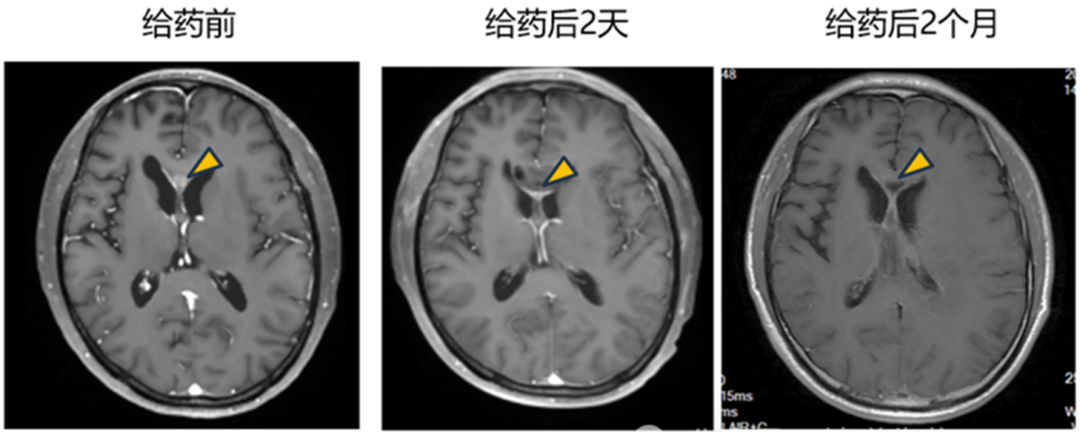

在瘤内注射患者中,观察到明确的治疗反应,靶病灶显著缩小超过 90%(图1)。

肿瘤切除+瘤腔内注射的1例患者,术后观察到肿瘤逐渐缩小并完全消退,达到影像学CR(complete response)(图2)。